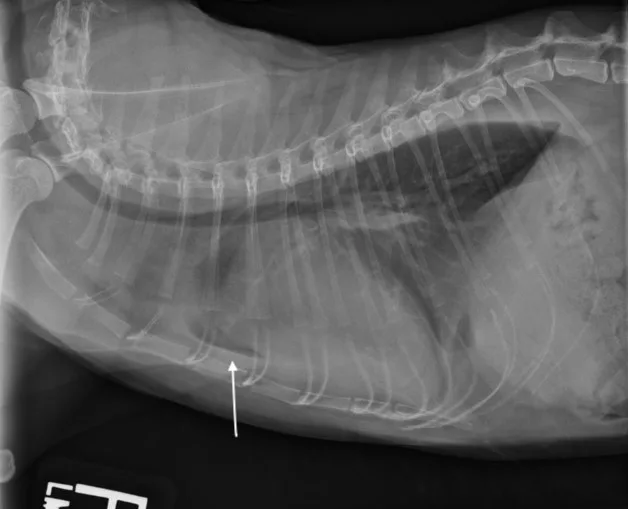

In cats, a ventral or diffuse interstitial-to-alveolar pattern may be present3,5; pleural effusion is indicated by pleural fissure lines, retraction of the lung lobes, and effacement of the cardiac silhouette.6 (See Figure 2.) Dyspneic cats with evidence of pulmonary infiltrates should receive a presumptive diagnosis of cardiogenic pulmonary edema until proven otherwise (often by a clinical diuretic trial).

Featured Image

FIGURE 2

L-CHF in a cat with cardiomegaly and pleural effusion with visible pleural fissure line (arrow).